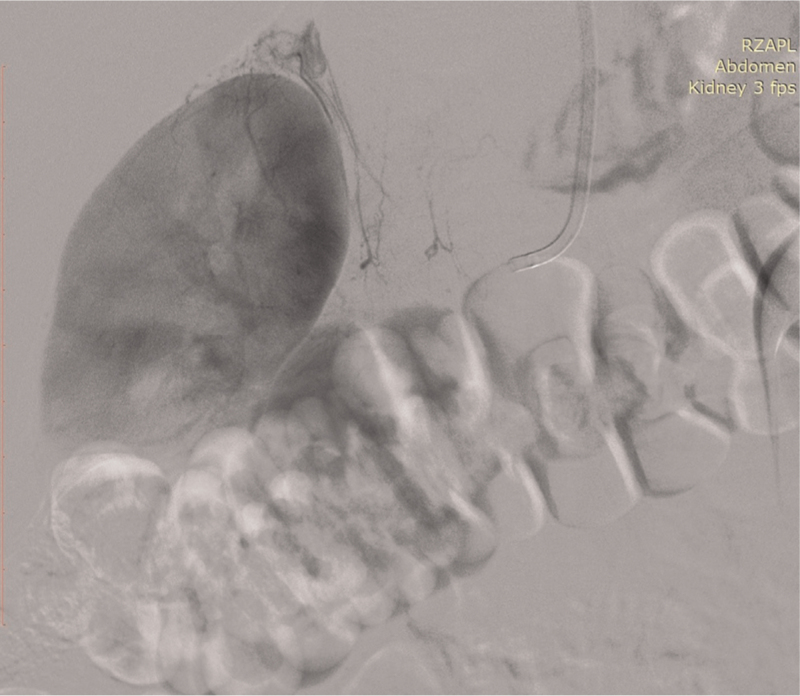

Abstract Image